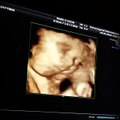

ต่าย ชุติมา อวดคลิปอัลตร้าซาวด์ลูกน้อย

rakball

10 years ago